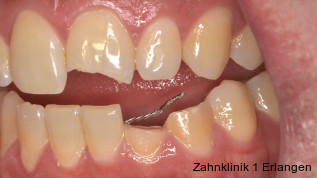

Zu den Zahnfrakturen mit Pulpabeteiligung gehören die in das Dentin reichende unkomplizierte Kronenfraktur sowie die komplizierte Kronenfraktur mit Pulpaexposition. Rein schmelzbegrenzte Frakturen sind hinsichtlich des Pulpastatus als unkritisch einzuschätzen.1 Dislokationsverletzungen betreffen die Pulpa insofern, als das Gefäß-Nerv-Bündel je nach Ausprägung der Positionsveränderung gestaucht, gedehnt oder abgerissen sein kann. Bei Zähnen mit abgeschlossenem Wurzelwachstum geht man davon aus, dass spätestens ab einer Dislokation von 2 mm die Pulpa abgerissen wurde, was die zeitnahe Einleitung der Wurzelkanalbehandlung notwendig macht.2, 3 Bei geringer ausgeprägter Dislokation kommt den Nachkontrollen eine wesentliche Rolle zu, bei denen jeweils dem Pulpastatus besonderes Augenmerk zukommen sollte, um eine Pulpanekrose frühzeitig zu detektieren.

Unkomplizierte Kronenfrakturen mit Verlauf im Dentin sind als Wundfläche einzuschätzen, bei der es bei anhaltender Exposition zum Mundhöhlenmilieu zur Infektion der Pulpa über freiliegende Dentintubuli kommen kann. Somit ist ein wesentlicher Grundsatz der Erstversorgung, die Dentinwunde abzudecken,3, 8 vor allem bei jungen Patienten mit großlumigen Dentintubuli. Die Abdeckung kann im Zuge der Notfallbehandlung mit Glasionomerzement erfolgen oder mittels fließfähigem Komposit unter Verwendung eines Dentinadhäsivs. Hilfreich im Hinblick auf die spätere Wiederentfernung ist dabei die Verwendung eines falschfarbenen oder opaken Materials, um die provisorische Abdeckung bei der definitiven Versorgung gezielt wieder entfernen zu können. Bei pulpanahen Verletzungen empfiehlt sich die Abdeckung mit einem biokompatiblen Material wie hydraulischem Kalziumsilikatzement oder Kalziumhydroxid im Sinne einer indirekten Überkappung.3 Betroffene Zähne können durch Wiederbefestigung des Zahnfragmentes9 oder mit Komposit restauriert werden, dies kann jedoch auch erst bei der Weiterbehandlung erfolgen.

Bei Pulpaexposition ist die oberste Prämisse der Erhalt der Vitalität des Zahnes. Vor allem bei jungen Patienten und bei nicht abgeschlossenem Wurzelwachstum, aber auch bei erwachsenen Patienten ist die Vitalerhaltung die Methode der Wahl. Dabei spielen die Dauer und die Größe der Exposition keine wesentliche Rolle.10 Die oberste Gewebeschicht sollte zunächst im Sinne einer Mikropulpotomie angefrischt werden, was mit einem Diamantschleifer unter Wasserkühlung durchgeführt werden kann. Nach Blutstillung, zu der Natriumhypochlorit tropfenweise appliziert werden kann, wird das Sistieren der Blutung kontrolliert. Ist dies verifiziert, wird ein biokompatibles Material in direktem Kontakt mit dem Gewebe aufgebracht und der Zahn anschließend adhäsiv verschlossen.10 Dauert die Blutung an, beispielsweise weil der Unfall bereits mehr als 24 Stunden zurückliegt, kann tiefer pulpotomiert werden. Da eine traumatisch geschädigte Pulpa in der Regel vor dem Unfall gesund war, ist die Heilungskapazität meist sehr gut.11 Auch bei bestehender Exposition zur Mundhöhle hin über einen Zeitraum von Tagen kann die Pulpotomie noch hohe Erfolgsraten erzielen.

Tierexperimentelle Studien konnten zeigen, dass selbst bei über mehrere Tage hinweg freiliegender Pulpa Bakterien aus der Mundhöhle nicht tiefer als 2 mm in das Gewebe eindringen konnten.12 Kritisch ist dabei die erfolgreiche Blutstillung, die nach ca. fünf Minuten erreicht sein sollte. Die Erfolgsquoten der Pulpotomie nach Zahntrauma liegen deutlich über denen der direkten Überkappung bei über 90 Prozent. Dies ist auch in der revidierten Fassung der S2k-Leitlinie zum dentalen Trauma bleibender Zähne herausgestellt.3 Es ist zu beachten, dass bei begleitender Dislokationsverletzung die Durchblutung der Pulpa eingeschränkt oder sogar komplett unterbunden sein kann, was das Risiko des Misserfolges vitalerhaltender Maßnahmen signifikant erhöht.13 Daher sollte in solchen Fällen die Pulpektomie durchgeführt werden. Dies gilt ebenso bei umfangreichem Hartsubstanzverlust, wenn die definitive Restauration zusätzlich intrakanalär verankert werden muss.